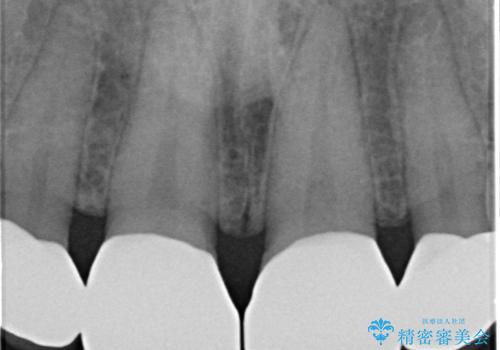

- 前歯の隙間を埋めたいとのことで来院された患者様です。

矯正治療とかぶせ物での治療どちらともご提案したところ、かぶせ物での治療をご希望されたためクラウンでの審美性回復を試みることとなりました。

今回のように、元の歯が小さすぎる場合は矯正治療での審美性回復が難しいことがあります。

形のイメージを反映させた仮歯を調整し、技工士さんと連携して製作したため口元に調和した非常に審美的なクラウンを装着することができました。